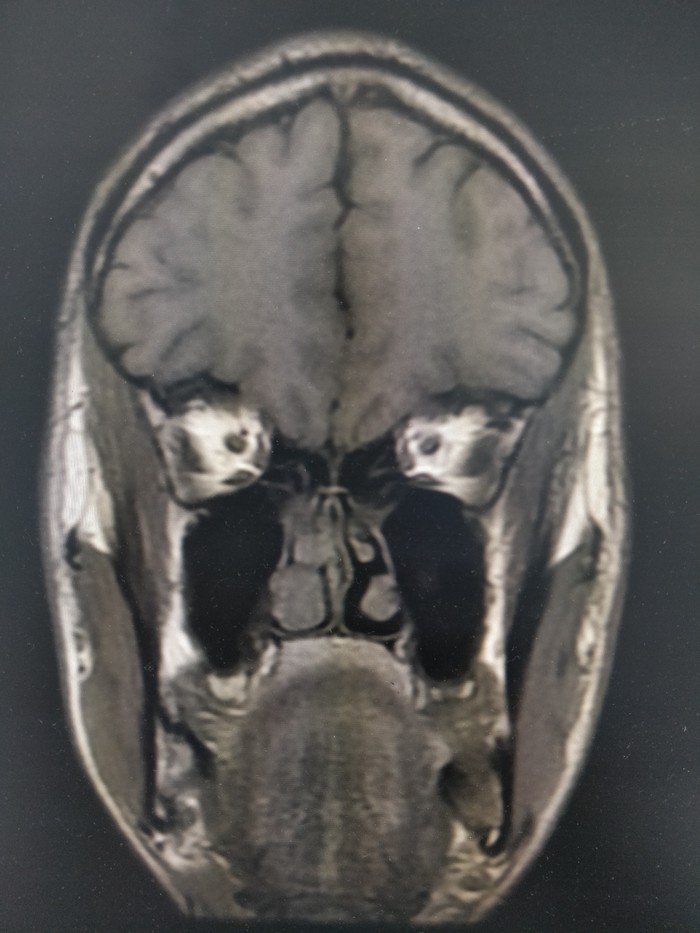

4. Ну а это, собсна, ваш покорный слуга с заложенным носом)